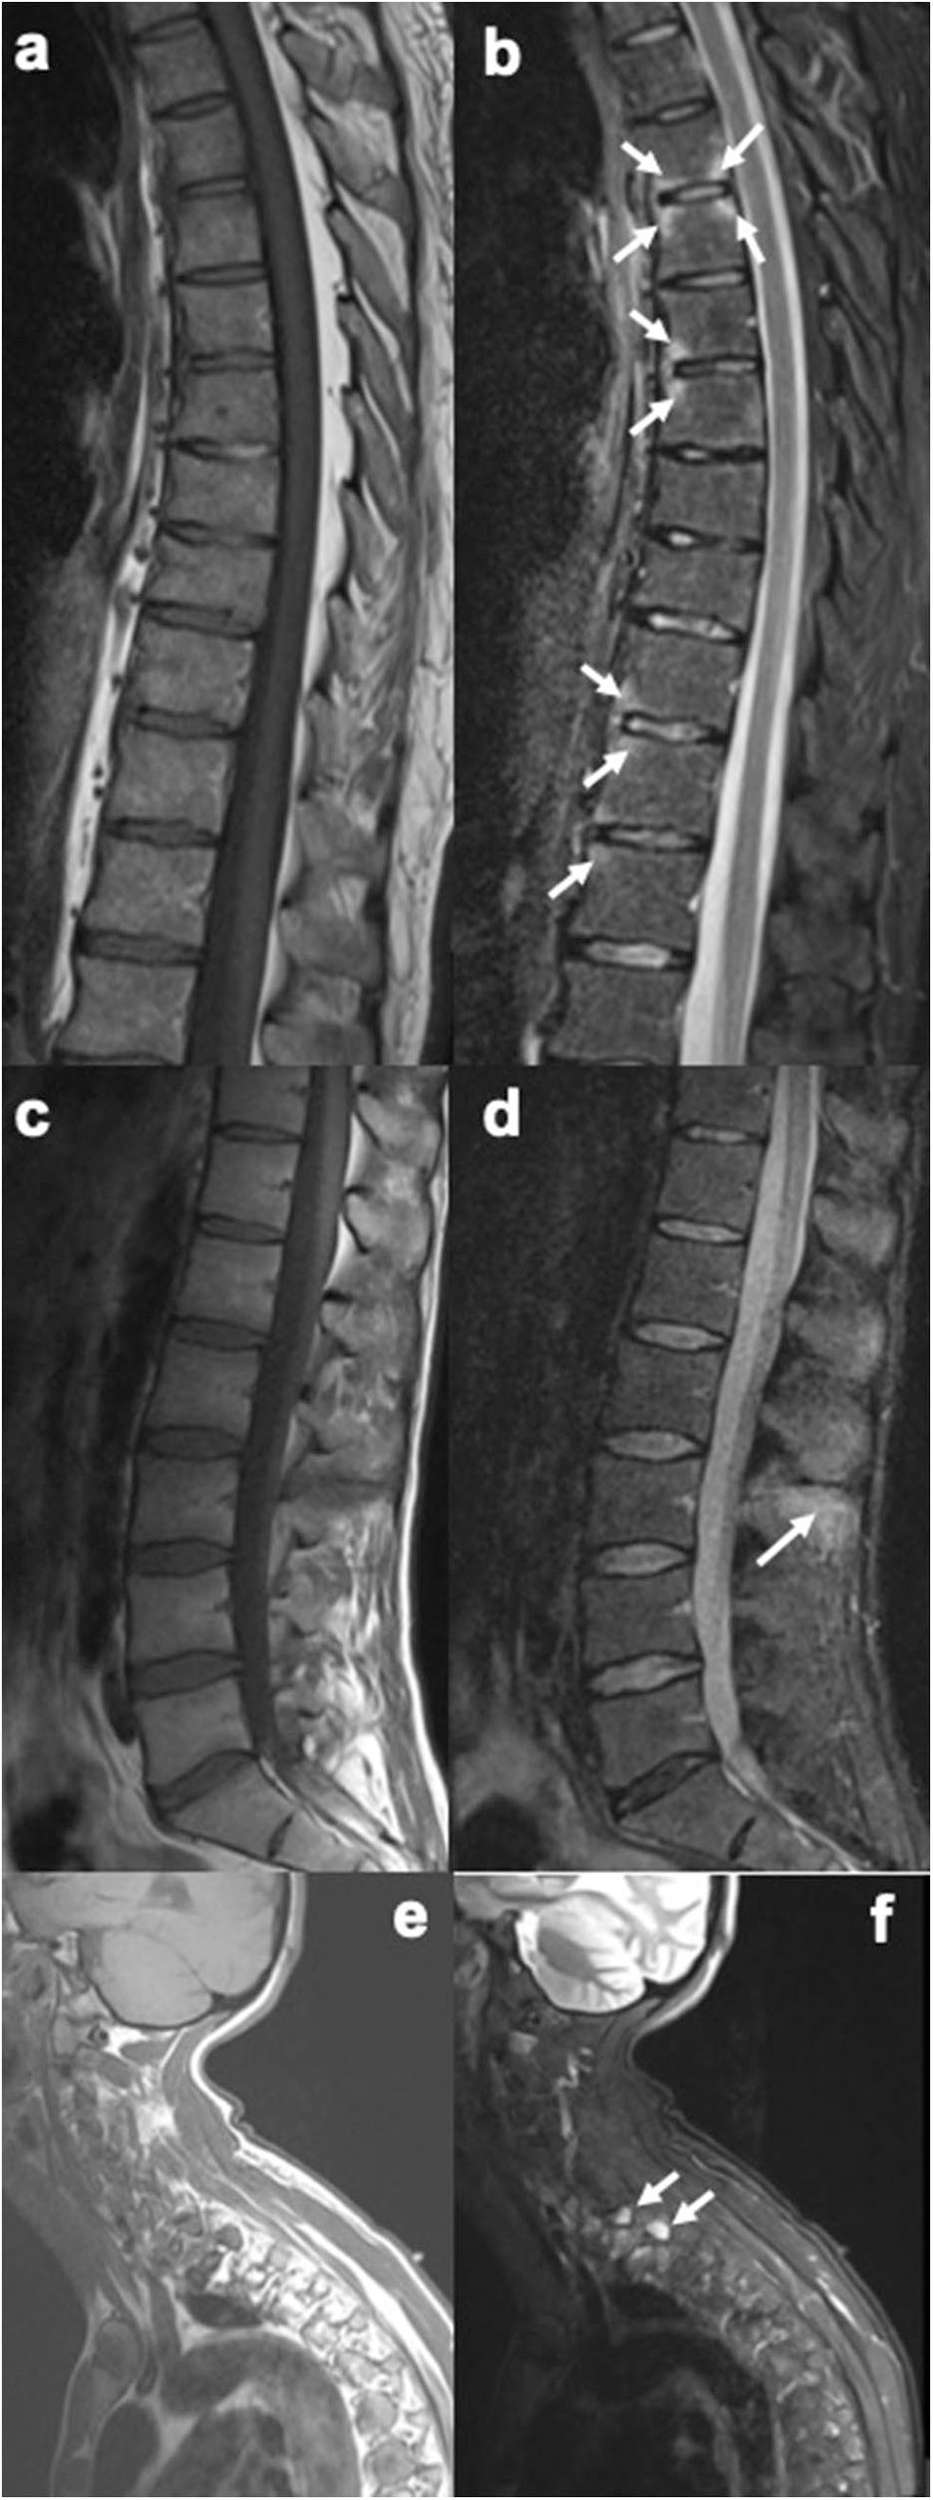

MRI is the imaging method of choice for diagnosing axial enthesitis. The revised definition of MRI enthesitis in sacroiliac joints of patients with SpA excludes the inter-osseous soft tissues in the ligamentary portion of the SI joint (35). Pelvic enthesitis on MRI of sacroiliac joints is highly specific for the diagnosis of SpA, and the specificity increases with the number of sites with enthesitis. Enthesitis at the iliac crest and retroarticular ligaments have high positive predictive value for diagnosis of SpA (36). Spinal enthesitis may be seen on spine MRIs as increased signal intensity over inter-spinal ligaments extending between the transverse or spinous processes, supra-spinal ligaments and osteitis of adjacent bone marrow in the spinous process on short tau inversion recovery (STIR) images, T2-weighted fat-suppressed images and contrast enhanced T1-weighted fat-suppressed images (37). The vertebral corners (or edges) are often inflamed in axial SpA and PsA, and this finding represents enthesitis at the insertions of the anterior and posterior longitudinal ligaments (38) (Figures 2a–f).

Figure 2. Sagittal MR images of the spine, showing enthesitis at different locations (T1-weighted images on the left, short tau inversion recovery (STIR) images on the right). (a,b) Several anterior and posterior corner inflammatory lesions (arrows) are seen in the thoracic spine, representing enthesitis at the insertion of the anterior and posterior longitudinal ligaments. (c,d) Bone marrow edema is seen at several spinous processes, particularly at the L3 spinous process (arrow), representing enthesitis. (e,f) Bone marrow edema is seen in two upper thoracic transverse processes (arrows), representing enthesitis. Images are from University of Copenhagen, Denmark.